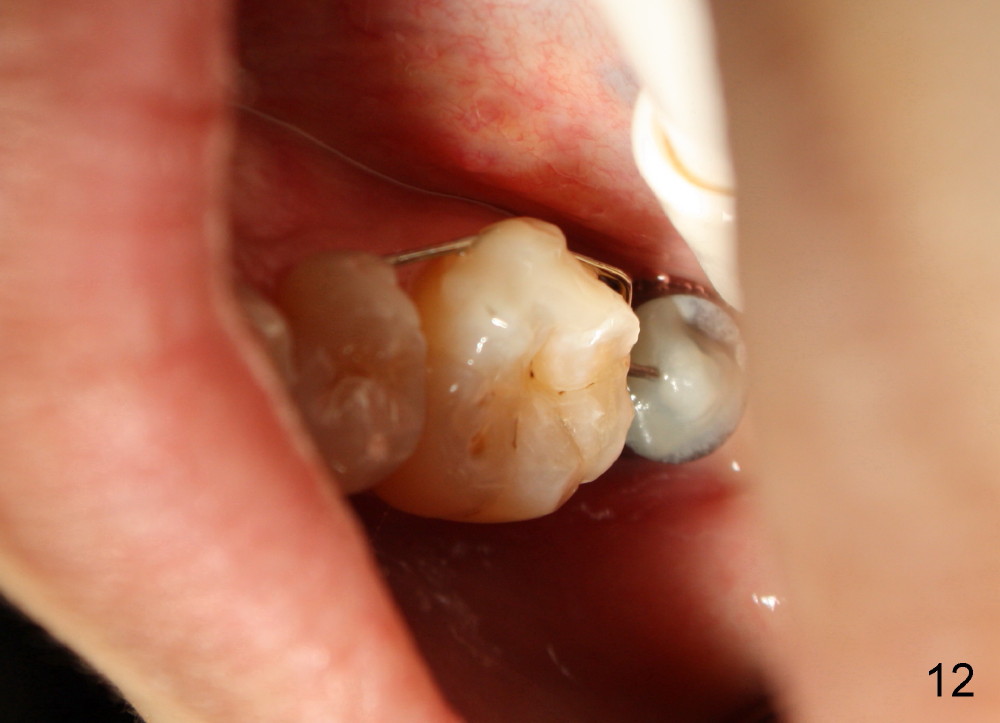

The lower left 2nd molar of a 45-year-old lady has perio-endo disease (Fig.1). The patient is not only very nervous, but also active in gag reflex. It is difficult to take good preop PA (Fig.1 *: ). Root canal therapy is performed. A relatively good PA is taken 1 year postop, again due to gap reflex (Fig.2). The tooth is still nonsalvageable (Fig.3). The last PA is taken 3.5 years before extraction and immediate implant. Infiltration anesthesia is administrated first. The patient experiences pain during early stage of osteotomy, but she does not report readily. Block anesthesia is added. Intraop PAs are taken with difficulty (Fig.4,5 with #1 sensor; 5 mm tap in place). Invasion of the inferior alveolar canal is not noted (Fig.5 dashed line). Oozing is a little more than expected. This is ignored. A 7x14 mm tapered implant is placed; the upper border of the inferior alveolar canal is not intact (Fig.6). Paresthesia area is defined next day (Fig.7). The implant is reversed for a few turns. Paresthesia area is reduced 19 days later (Fig.8). The implant is not stable. Follow up PAs are taken with difficulty (Fig.9-11). It appears that a shorter cylindrical implant is more appropriate for this case (Fig.11). The implant is stabilized with splinting with questionable result (Fig.12).